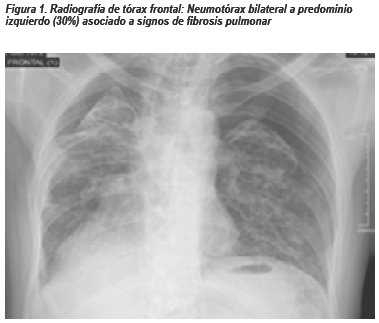

PRESENTACIÓN DEL CASO

Paciente varón de 42 años natural y procedente de Lima, sin antecedentes médicos de importancia, con diagnóstico de Meduloblastoma Cerebeloso operado en el 2005 (craneotomía suboccipital izquierda + resección total de tumor), recibió adyuvancia con radioterapia y quimioterapia la cual consistió en 10 cursos de Carmustina (BCNU)yVincristina con regular tolerancia. Acude a control en Agosto 2016, refirió tiempo de enfermedad de 3 meses caracterizado por disnea a grandes esfuerzos la cual empeora súbitamente en la última semana. Al examen físico: paciente hemodinámicamente estable, taquicárdico, saturación de oxígeno 92%. La radiografía de tórax frontal muestra neumotórax bilateral a predominio izquierdo y signos sugestivos de fibrosis pulmonar.